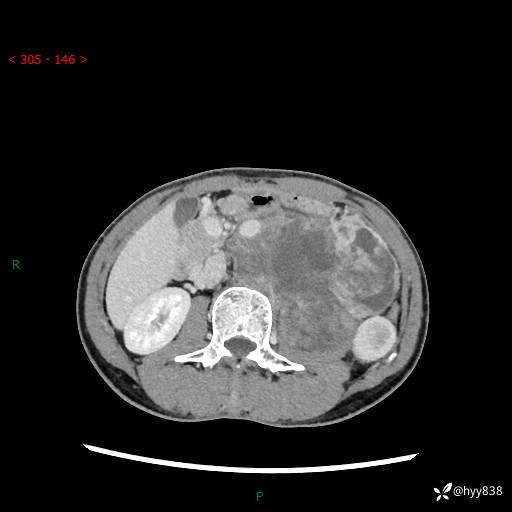

简要病史:患者无明显诱因出现左侧下腹及左侧腰背部疼痛,为间歇性隐痛,我院行胃肠镜检查,提示慢性非萎缩性胃炎,予以口服药物治疗,效果欠佳,后仍觉腹痛不适,遂至当地中医医院就诊,行彩超提示左肾积水及左肾实质性占位,遂来我院泌尿外科就诊

腹部CT平扫+增强